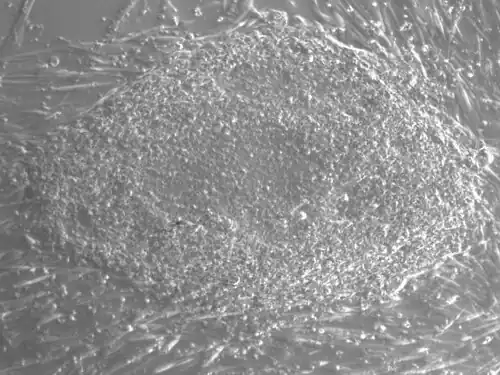

Une colonie de la lignée de cellules souches embryonnaires humaine HD90 dérivée au CHRU de Montpellier.